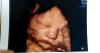

А в этот раз сказали к родам ждать 3500кг) ну посмотрим, походить бы ещё минимум неделю, было бы вообще отлично! Ну и моё щекастое счастье)

Вообще у меня было 2д узи, а узистка включила 3д на мониторе показала личико и вот ещё 2 фоточки сделала. Обычно 1 фото - 100руб. А узистка бесплатно дала)